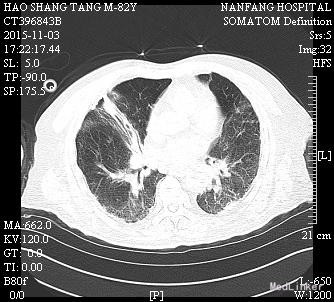

男,82岁,已婚,因“肢体抽搐伴意识障碍1天“入我院神经内科,因肺部感染加重10天后转入呼吸内科

入神经内科经舒普深抗感染及抗癫痫等治疗,无明显癫痫,但肺部感染加重,查见广泛耐药鲍曼不动杆菌及铜绿假单胞菌感染,转入呼吸科后给予美平联合舒普深治疗,1周后成功拔管脱机,2周后体温完全正常,转入康复科继续治疗